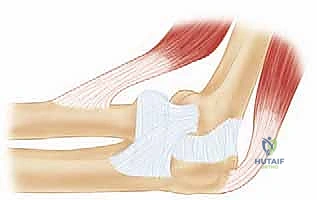

لفهم عبقرية جراحة استبدال رأس الكعبرة المعيارية، يجب أولاً أن نفهم التشريح المعقد لمفصل الكوع. الكوع ليس مجرد مفصل بسيط يعمل كالمفصلة (Hinge Joint)، بل هو مفصل مركب يتكون من ثلاثة مفاصل فرعية تعمل بتناغم تام:

1. المفصل العضدي الزندي (Ulnohumeral Joint): المسؤول الأساسي عن حركة الثني والفرد.

2. المفصل العضدي الكعبري (Radiocapitellar Joint): حيث يلتقي رأس الكعبرة بعظمة العضد.

3. المفصل الكعبري الزندي القريب (Proximal Radioulnar Joint): المسؤول عن حركة دوران الساعد (الكب والاستلقاء - Pronation & Supination).

دور رأس الكعبرة في استقرار الذراع:

رأس الكعبرة يشبه "ممتص الصدمات" الأساسي في الكوع. فهو يتحمل حوالي 60% من القوى الضاغطة التي تنتقل من اليد إلى الكوع. علاوة على ذلك، يُعتبر رأس الكعبرة المُثبِّت الثانوي الأساسي ضد قوى الانحناء الخارجي (Valgus Stress). عندما يتم استئصال رأس الكعبرة بالكامل دون استبداله (كما كان يحدث في الطب القديم)، يعاني المريض من عدم استقرار مزمن، هجرة عظمة الكعبرة للأعلى، وألم مبرح في مفصل الرسغ.